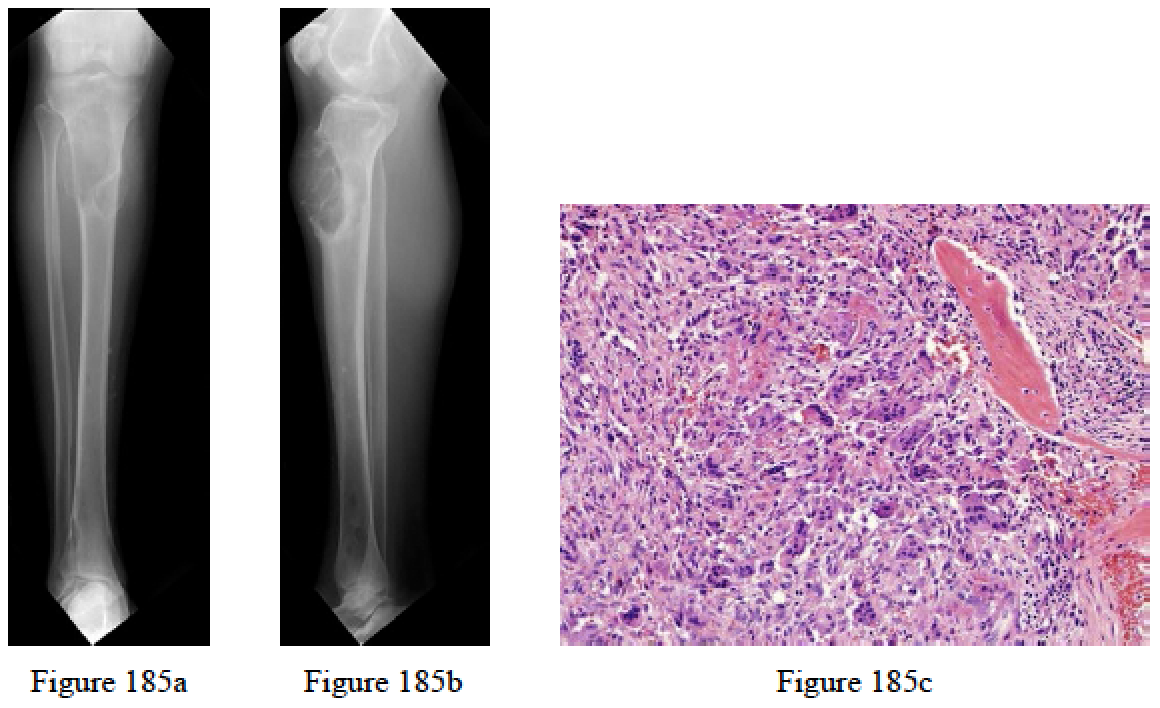

- Figures 185a through 185c are the biopsy specimen and radiographs of a 43-year-old man with a slowly enlarging mass in his right proximal tibia. He has normal kidney function. Examination reveals a firm mass with slight tenderness. Which laboratory value is most likely elevated?

- Serum calcium

- Serum phosphorous

- Serum gamma globulin

- Serum creatine phosphokinase

- Prostate-specific angiten

- Serum calcium

RECOMMENDED READINGS

Singhal S, Johnson CA, Udelsman R. Primary hyperparathyroidism: what every orthopedic surgeon should know. Orthopedics. 2001 Oct;24(10):1003-9; quiz 1010-1. Review. PubMed PMID: 11688768.

Mankin HJ, Mankin CJ. Metabolic bone disease: a review and update. Instr Course Lect. 2008;57:575-93.Review. PubMed PMID: 18399611.